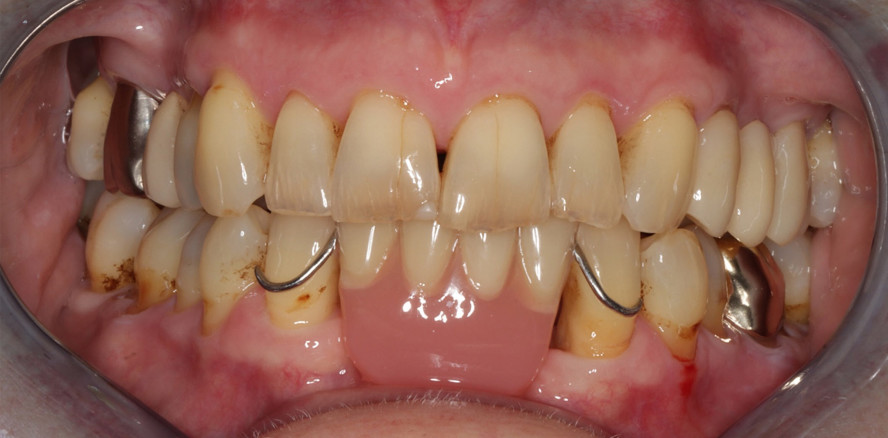

Foto: Dr. Christoph Schoppmeier

Trotz der hohen Prävalenz und der ernsthaften gesundheitlichen Folgen bleibt die Erkrankung oft unerkannt und wird dementsprechend nicht adäquat behandelt. Daher ist es von entscheidender Bedeutung, das Bewusstsein für diese Erkrankung zu schärfen und effizientere Strategien zur Prävention, Diagnostik und Therapie von Mundtrockenheit zu entwickeln. [Abb. 1]